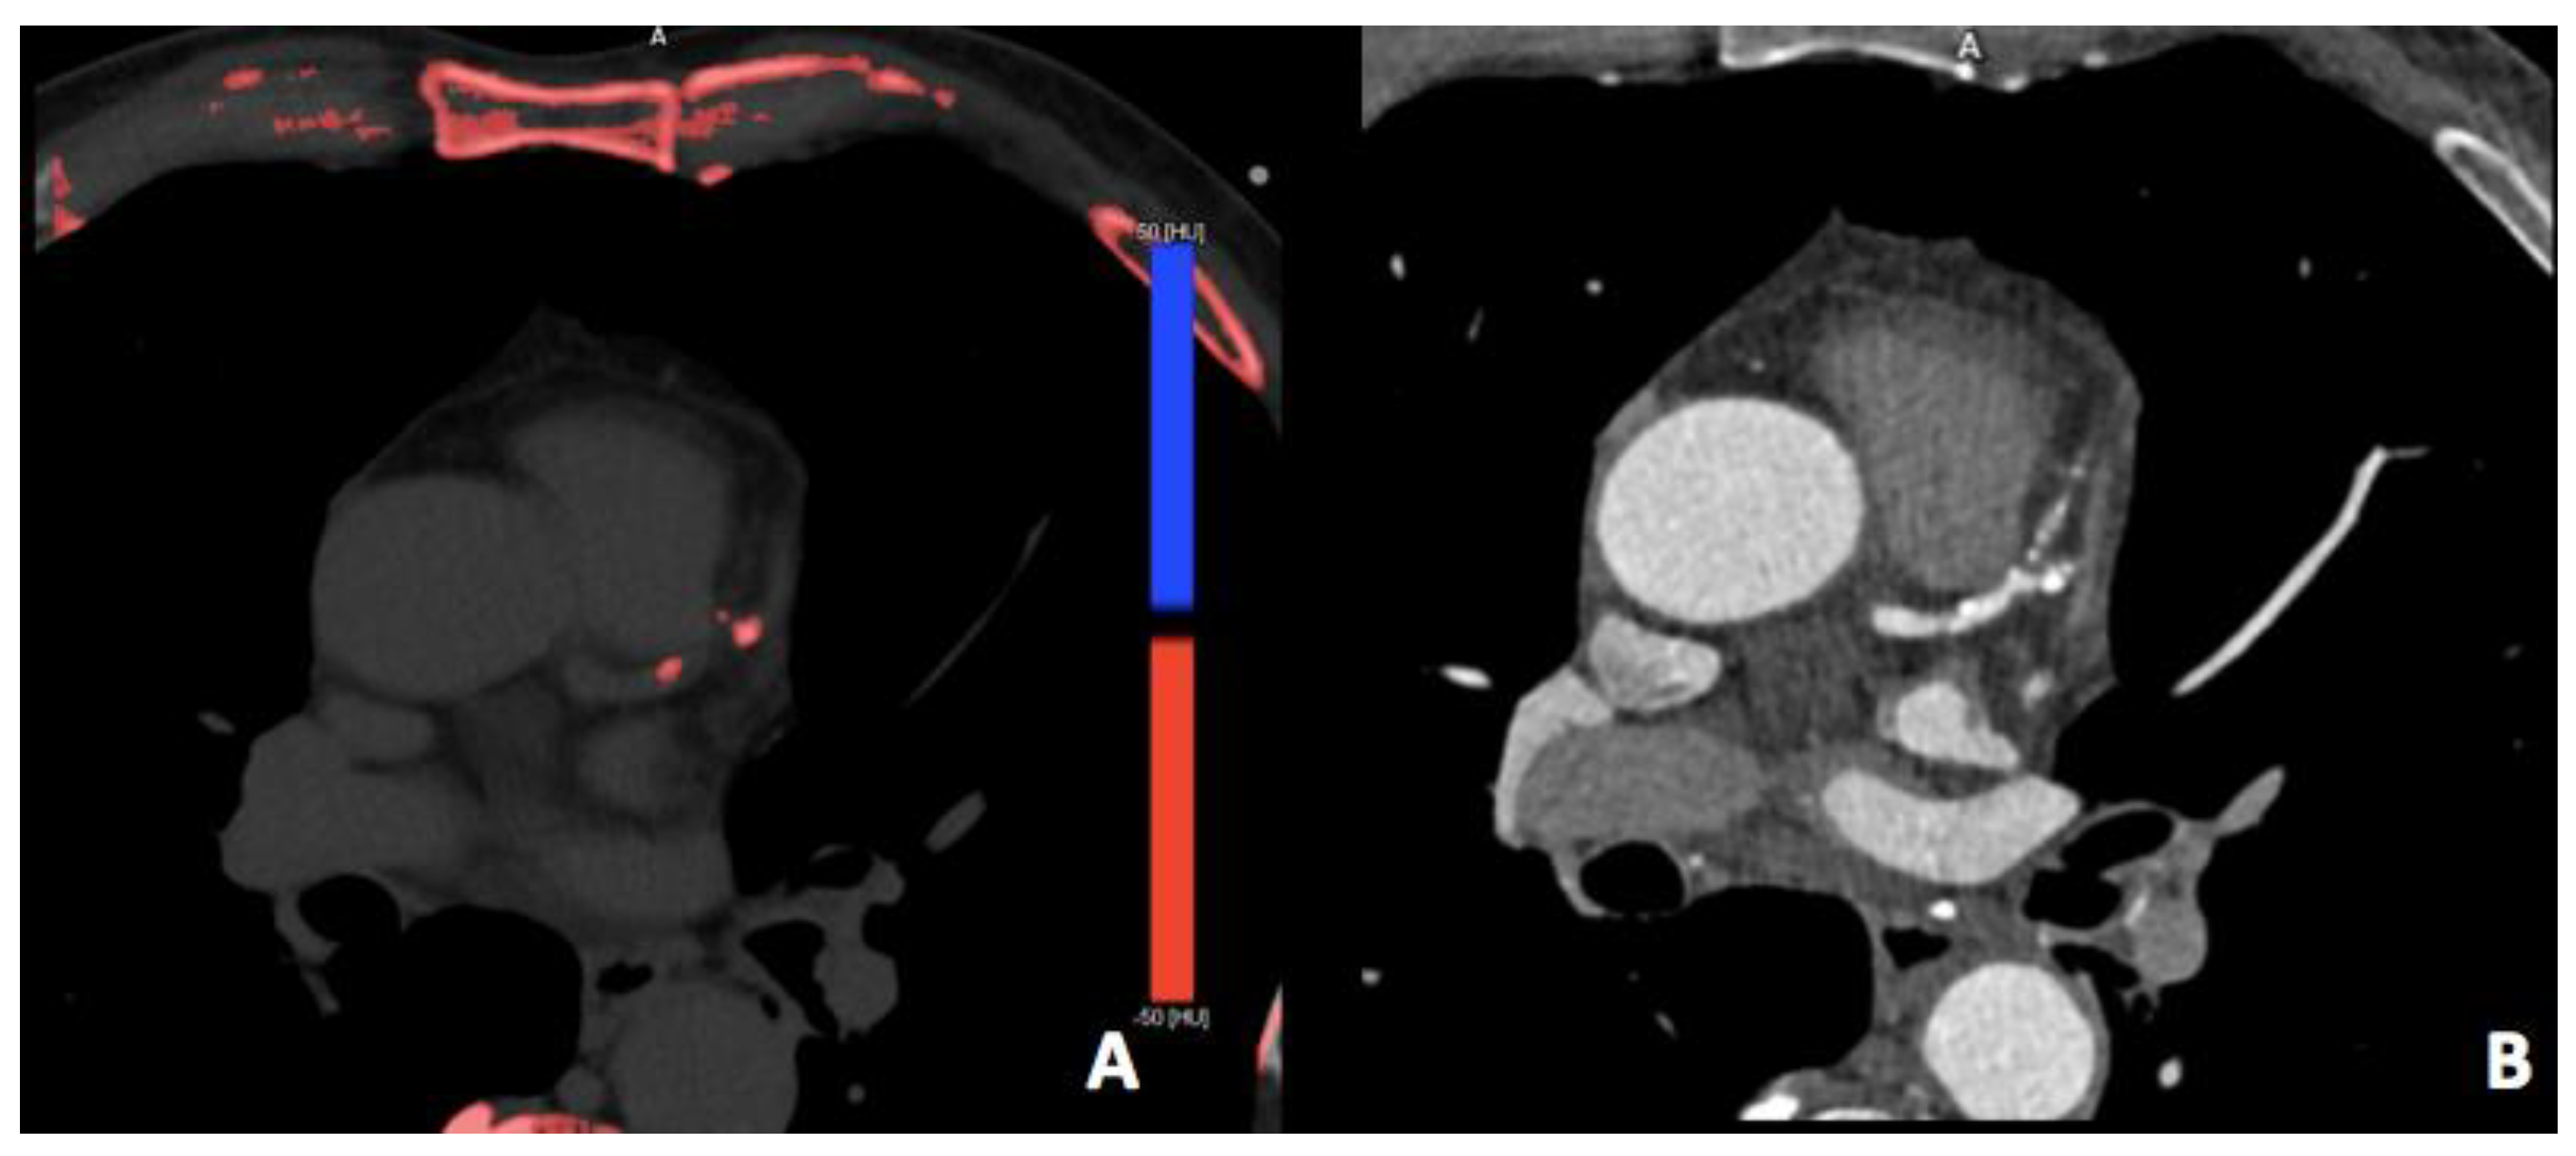

3.2. Virtual Non-Contrast Imaging

- Song, I.; Yi, J.G.; Park, J.H.; Kim, S.M.; Lee, K.S.; Chung, M.J. Virtual Non-Contrast CT Using Dual-Energy Spectral CT: Feasibility of Coronary Artery Calcium Scoring. Korean J. Radiol. 2016, 17, 321–329. [Google Scholar]

- Machida, H.; Tanaka, I.; Fukui, R.; Shen, Y.; Ishikawa, T.; Tate, E.; Ueno, E. Current and Novel Imaging Techniques in Coronary CT. RadioGraphics 2015, 35, 991–1010. [Google Scholar] [CrossRef] [PubMed]

- Yamada, Y.; Jinzaki, M.; Okamura, T.; Yamada, M.; Tanami, Y.; Abe, T.; Kuribayashi, S. Feasibility of coronary artery calcium scoring on virtual unenhanced images derived from single-source fast kVp-switching dual-energy coronary CT angiography. J. Cardiovasc. Comput. Tomogr. 2014, 8, 391–400. [Google Scholar] [PubMed]

- Foley, W.D.; Shuman, W.P.; Siegel, M.J.; Sahani, D.V.; Boll, D.T.; Bolus, D.N.; De Cecco, C.N.; Kaza, R.K.; Morgan, D.E.; Schoepf, U.J.; et al. White Paper of the Society of Computed Body Tomography and Magnetic Resonance on Dual-Energy CT, Part 2. J. Comput. Assist. Tomogr. 2016, 40, 846–850. [Google Scholar]